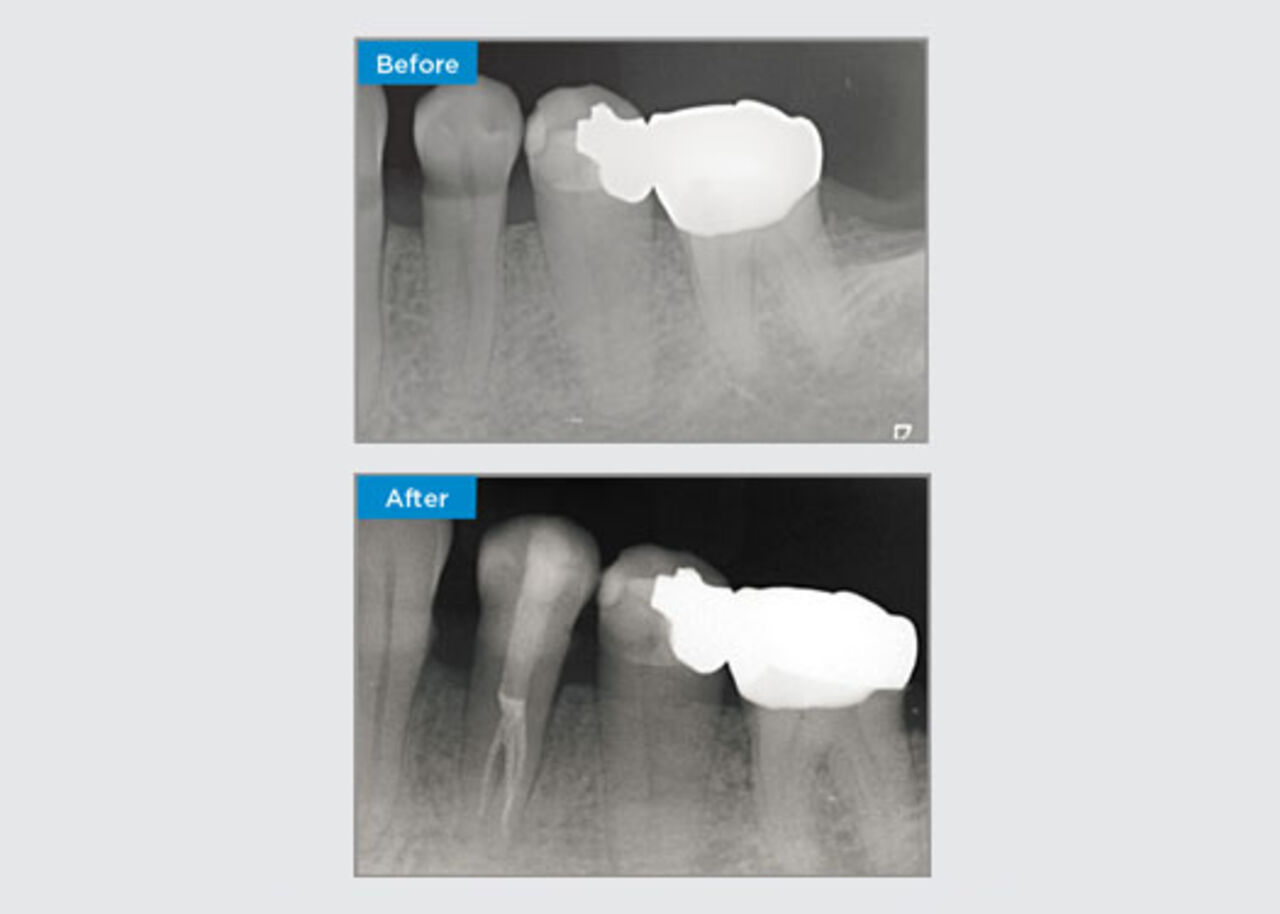

A 35 year old female patient presented after referral from a Specialist Periodontist. During the initial endodontic assessment the patient mentioned crown lengthening had been performed, prior to placement of the crown on tooth 16, two years earlier. Two months prior to the patient presenting, she had noted swelling of the palatal gingiva. The patient’s general dental practitioner had discovered a 7mm periodontal pocket adjacent the palatal sinus tract associated with tooth 16. The patient was referrred to a Specialist Periodontist. The Specialist Periodontist diagnosed a primary endodontic - secondary periodontal lesion. The patient had satisfactory oral hygiene and was a regular dental attender. Tooth 16 was tender to percussion. It was noted that the crown margins were satisfactory and the periodontal pockets around tooth 16 were less than 2mm deep on the buccal aspect, however on the palatal surface, adjacent the sinus tract there was a 6.5mm isolated periodontal pocket. Thermal testing of tooth 16 revealed a negative response. Tooth 16 had risk factors for apical periodontitis such as: a negative response to thermal testing, tenderness to percussion, a history of a deep restoration following crown lengthening surgery and radiographically identifiable periapical disease. Tooth 16 did not have a history of pain on biting or chewing, which may indicate a crack communicating with the pulp and/or periodontal tissues. The patient had no risk factors for periodontal disease and there was no abnormally deep pocketing present around any other teeth.

Dr Omar Ikram, Endodontist, Crows Nest, NSW Australia